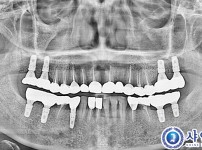

뼈이식임플란트 18개 - 스트라우만록솔리드